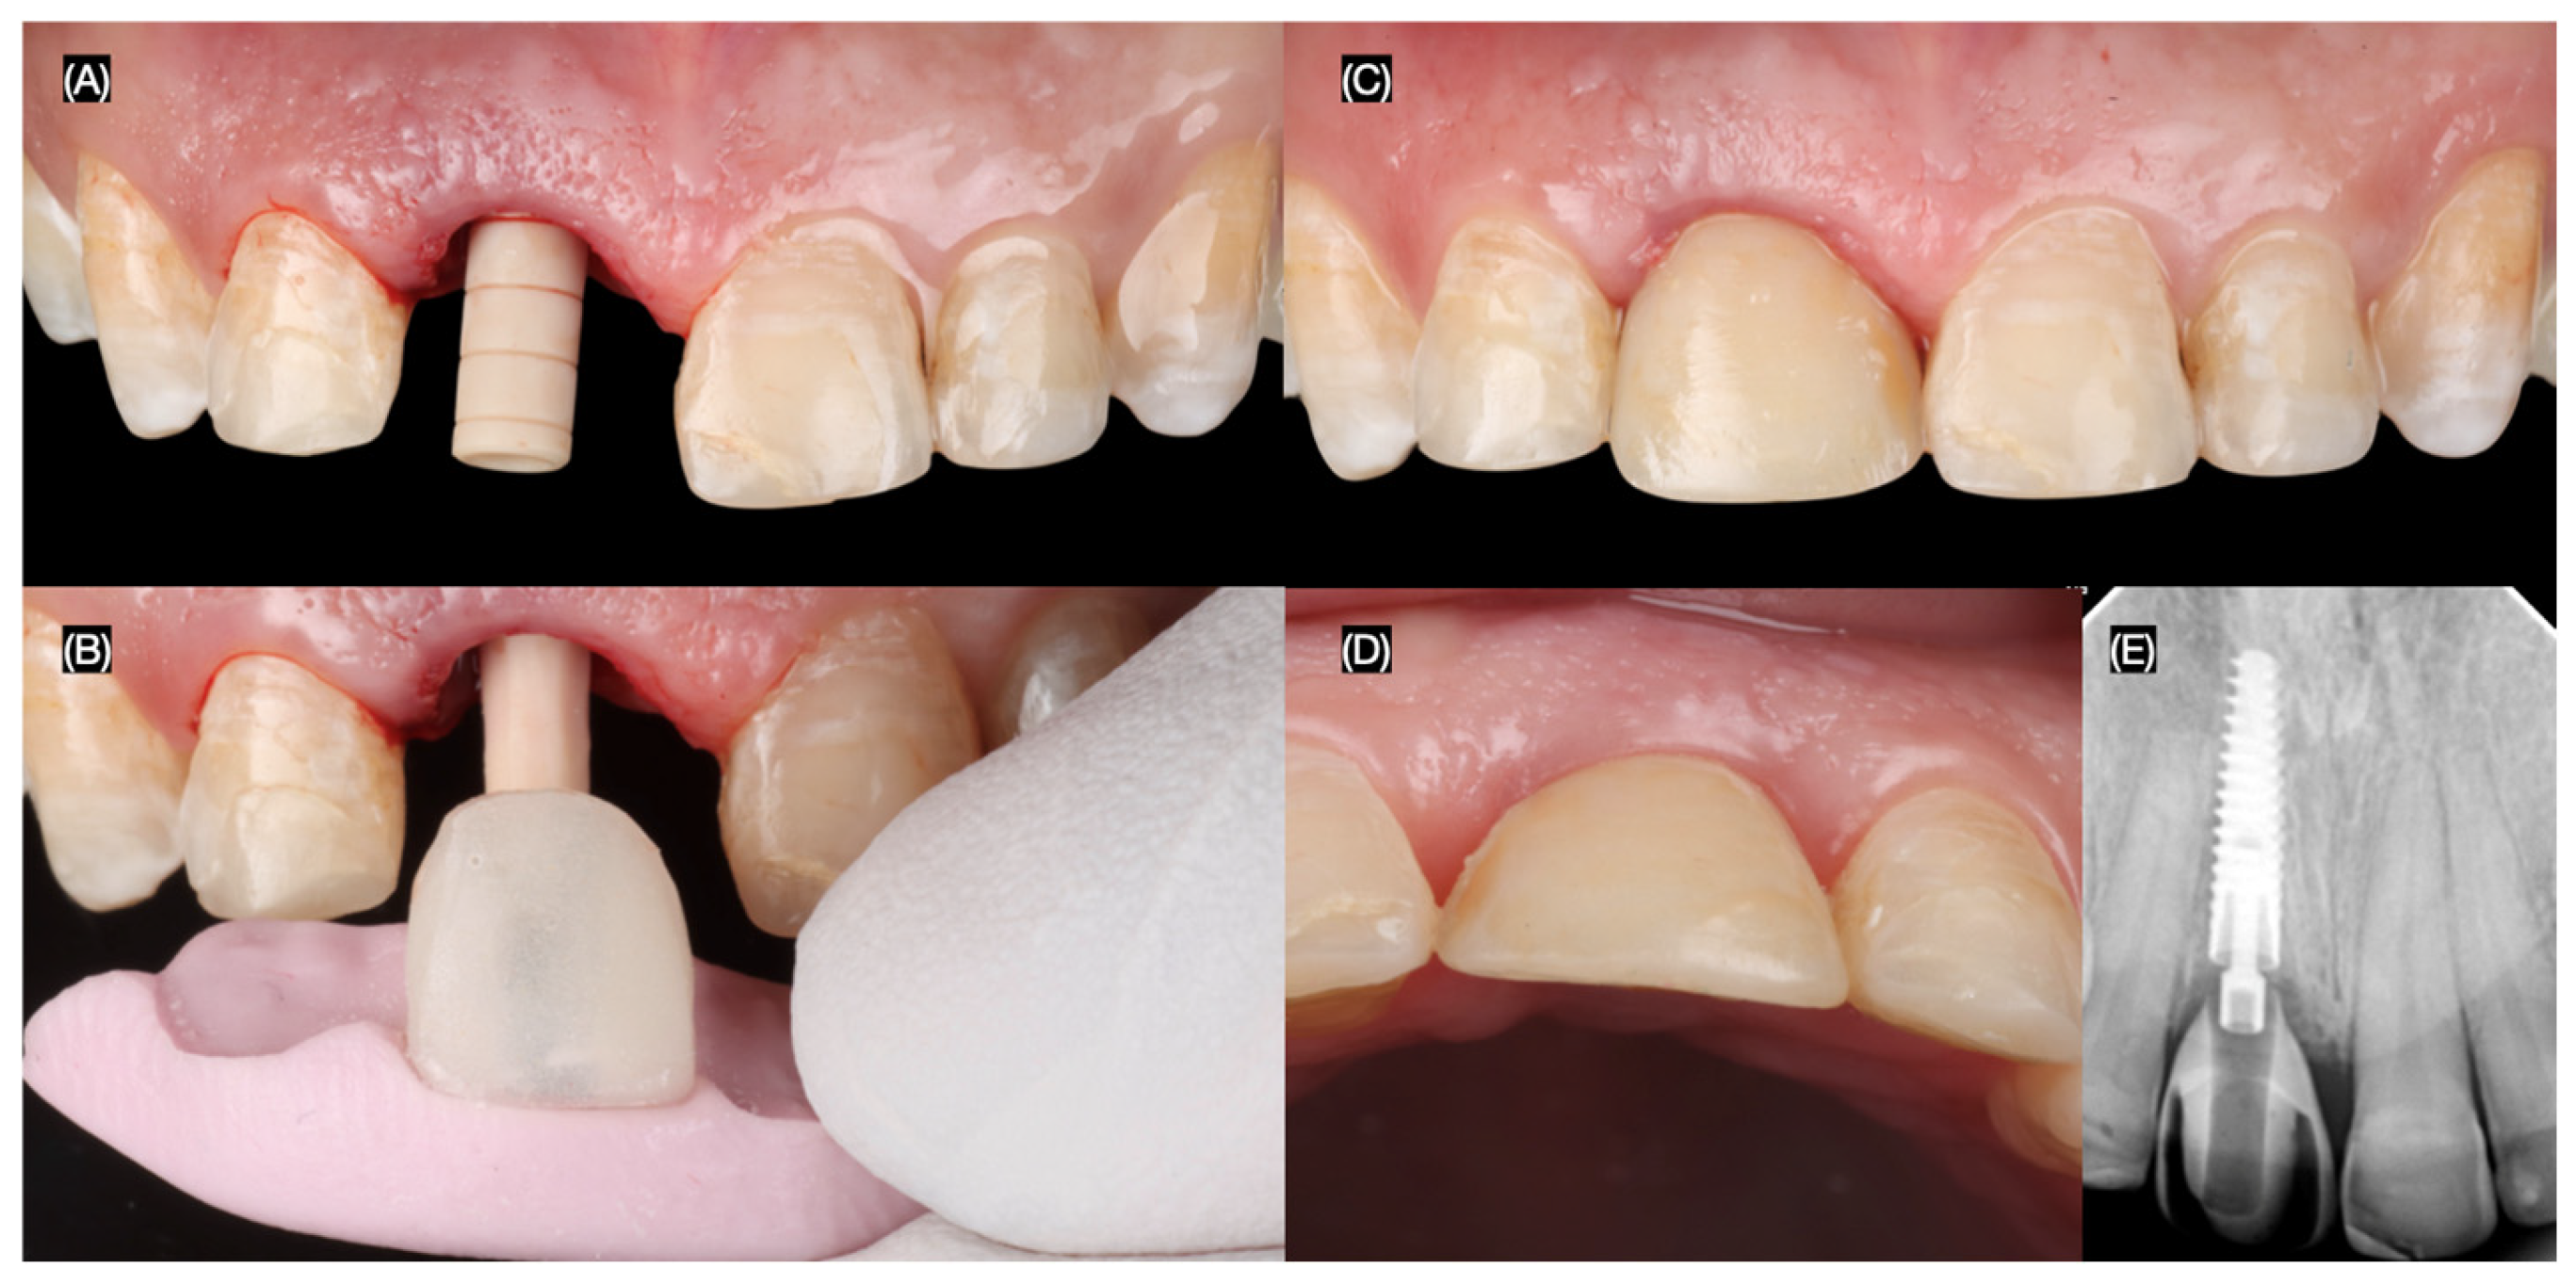

Following the implant placement, a screw-retained provisional restoration (Structure Premium, VOCO GmbH, Cuxhaven, Germany) was immediately placed. The provisional restoration was carefully adjusted to be out of occlusion to minimize micromovements that could compromise osseointegration and potentially lead to implant failure (Figure 6).

Figure 6.

Implant provisional restoration. (A) Interim implant post; (B) placement of the interim crown with putty index, interim crown, (C) frontal, and (D) incisal view; and (E) radiograph.